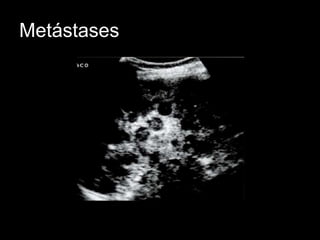

Metástases

• 50% dos pacientes com neoplasias

malignas

• Restritas ao baço – raro

• Disseminação por via hematogênica é

mais frequente

• Linfoma, carcinoma de pulmão, mama,

melanoma maligno

• Aspecto variado

Metástases • 50% dospacientes com neoplasias malignas • Restritas ao baço – raro • Disseminação por via hematogênica é mais frequente • Linfoma, carcinoma de pulmão, mama, melanoma maligno • Aspecto variado